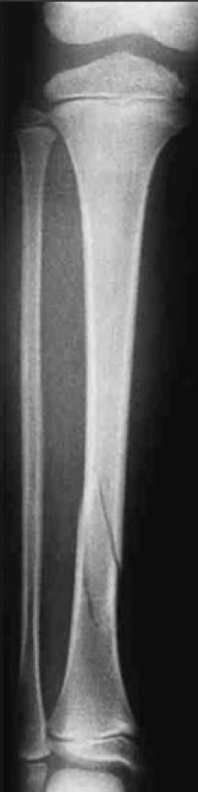

A pattern of fracture that spirals part of the length of a long bone

Spiral